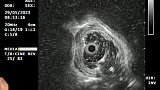

Иллюстрация №4: Микрофото. Г-Э х200. Сидероз пищевода

Эндоскопическое заключение было подтверждено данными патоморфологического исследования, согласно которому, в биоптате слизистой оболочки пищевода были обнаружены фрагменты поверхностных отделов слизистой оболочки, в субэпителиальной соединительной ткани которых обнаруживаются немногочисленные клетки с бурым пигментом в цитоплазме – картина сидероза (Рис.4)

Патолого-гистологическое заключение

В препарате мелкие фрагменты поверхностных отделов слизистой оболочки пищевода, в субэпителиальной соединительной ткани которых обнаруживаются немногочисленные клетки с бурым пигментом в цитоплазме. Опухолевого роста в пределах данного материала нет.